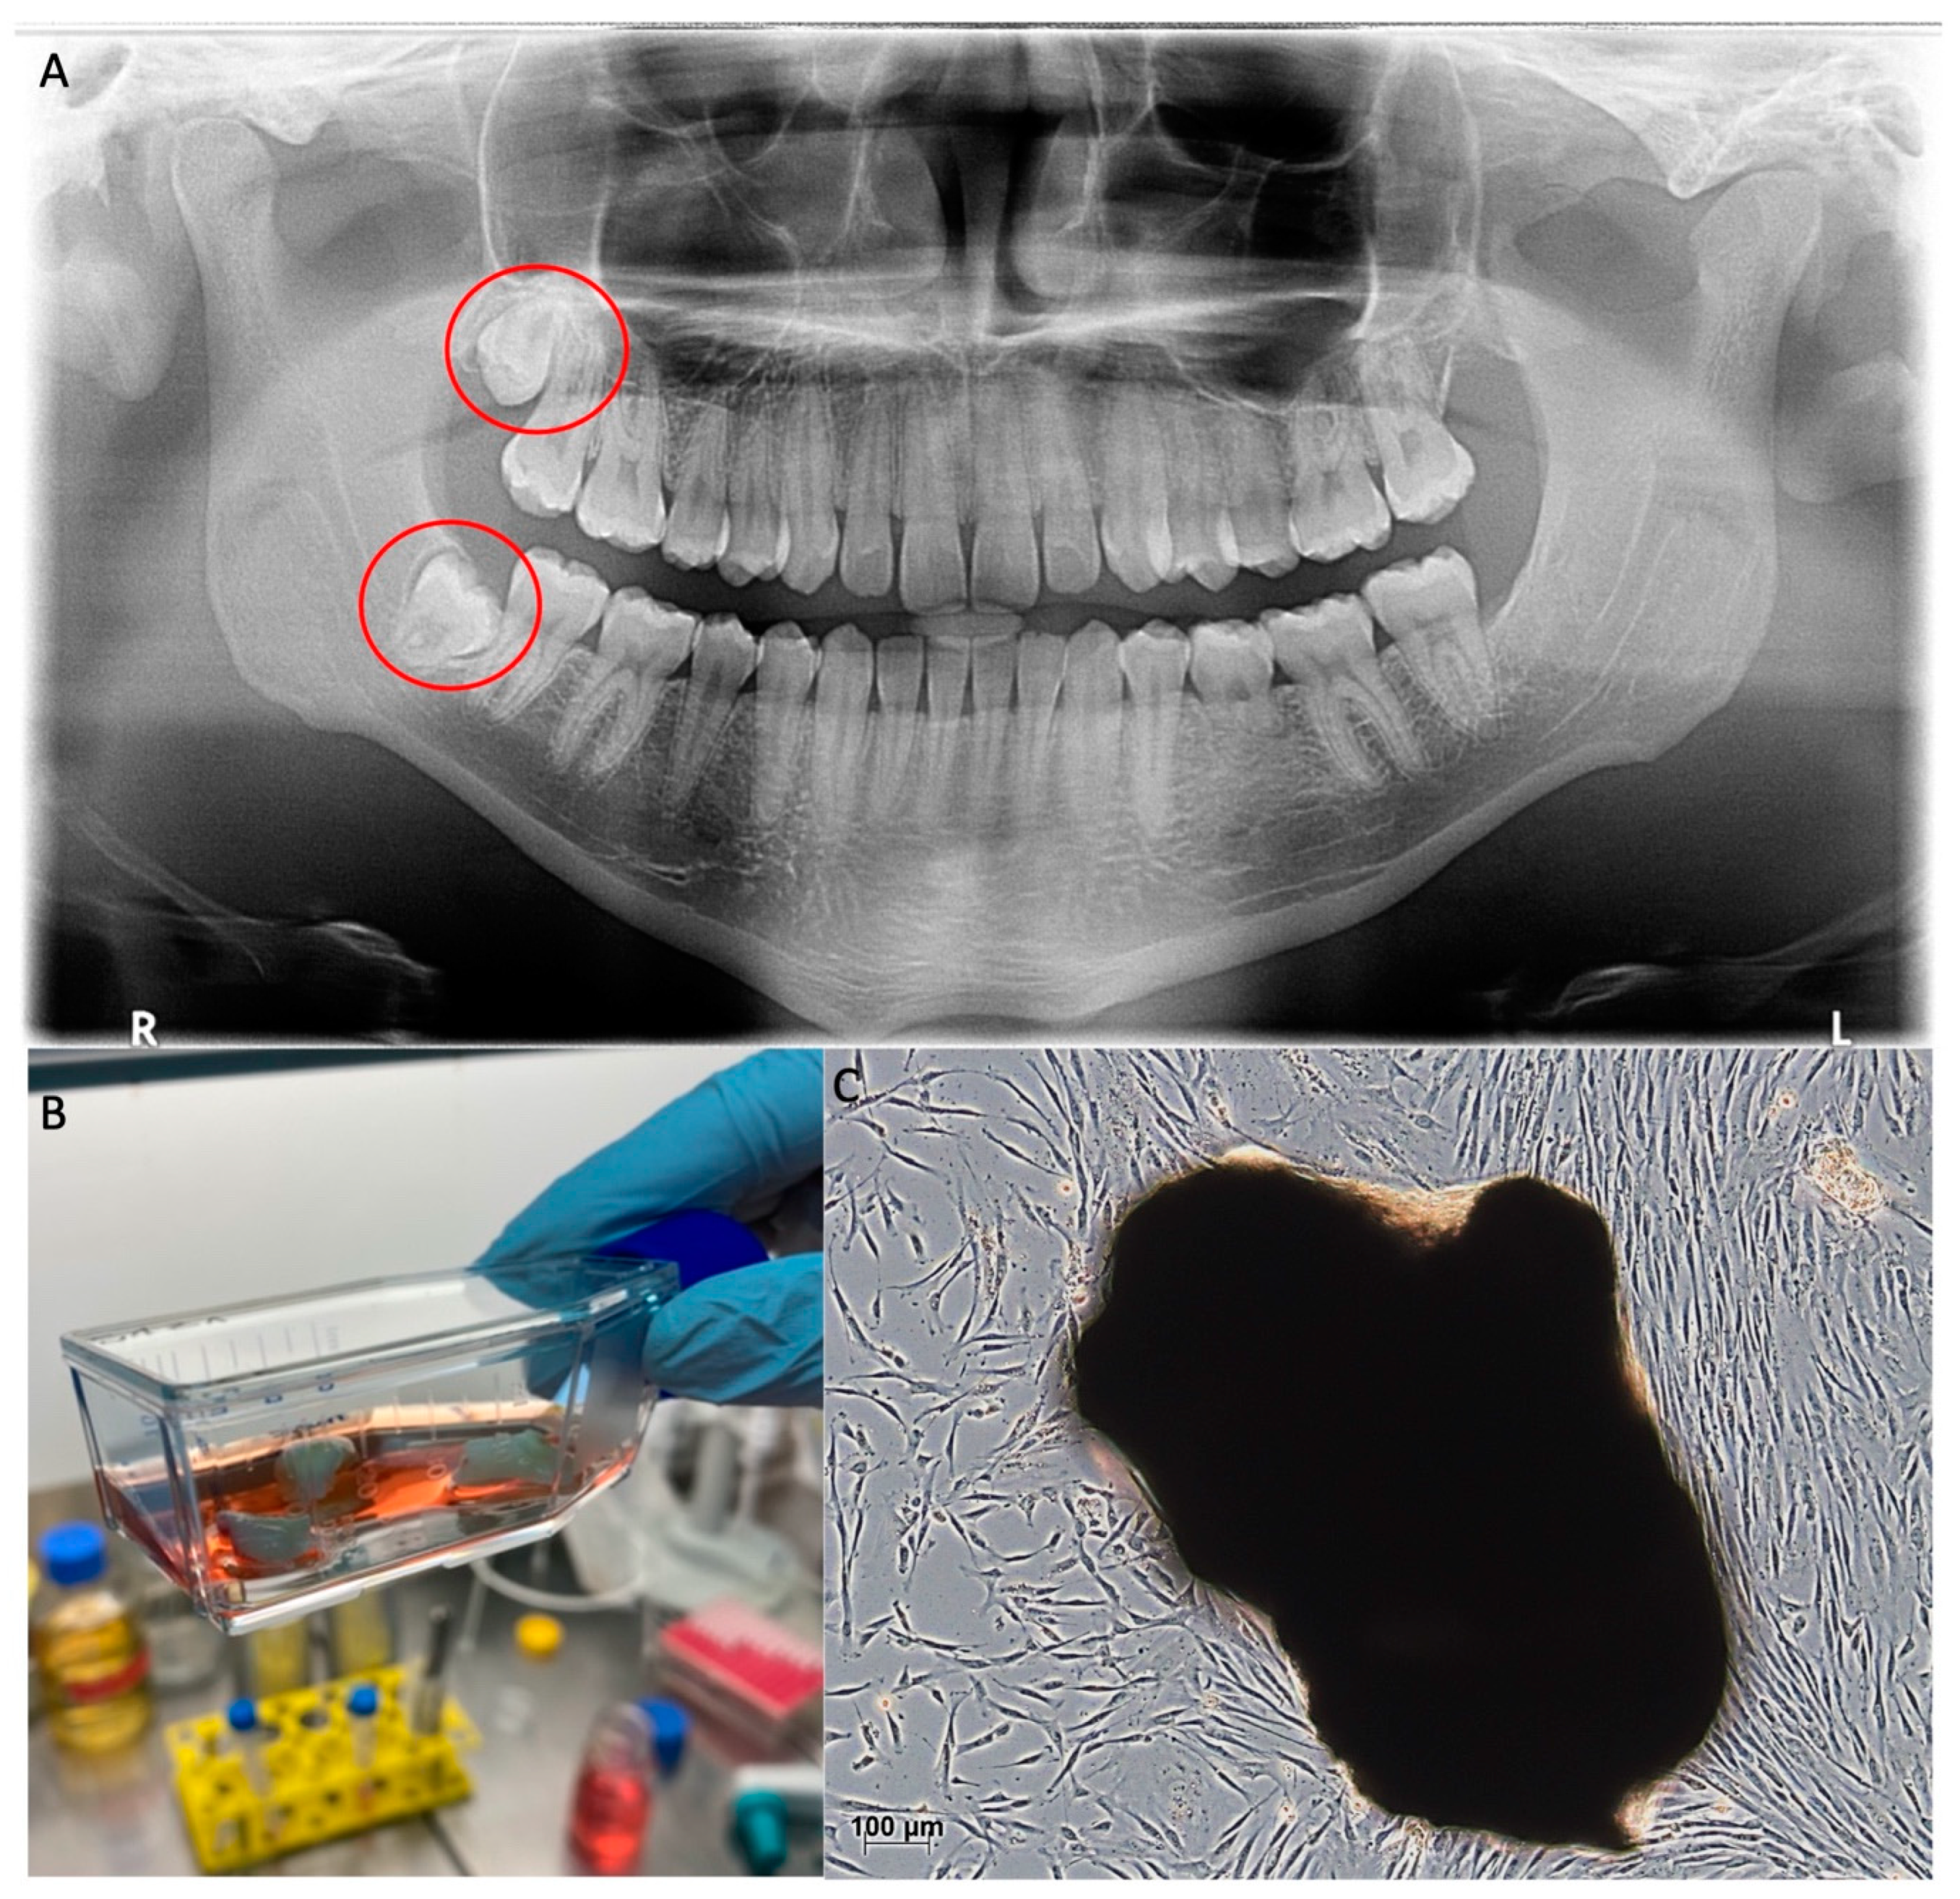

To implement stem cell therapy in the clinic, easy and harmless accessibility to the cells is essential. For this reason, dental pulp stem cells (DPSC), which originate from the neural crest, have been the focus of regenerative medicine since their first description in 2000 [35,36,37,38]. DPSCs can be easily isolated from the pulp of extracted third molars in many different ways. One way is the incubation of cut teeth in a culture flask, as shown in Figure 1B. This method brings the risk of contamination with oral bacteria, which is why the extracted teeth should be preserved in the antibiotic medium for at least 12 h after extraction. The advantage of this method is the weighting of the pulp tissue, which ensures direct contact of the cells with the culture flask’s ground. This contact is necessary for the cells to attach to the ground and start migrating into the flask. To reduce the risk of contamination, the pulp can be peeled off the cracked tooth and put into the culture flask on its own (Figure 1C). This technique requires a higher level of experience, since the risk of the tissue floating away in the culture medium is higher.

Figure 1.

Harvesting of DPSCs; (A): Third molars in situ marked with red circles (panoramic X-ray); (B): Extracted third molars, split and digested in collagenase for explant culture; (C): DPSCs emigrating from dissolved pulp tissue (dark mass) and adhering to the culture flask investigated by light microscopy. This figure belongs to David Muallah, Department of Oral and Maxillofacial Surgery, University Hospital Hamburg-Eppendorf.